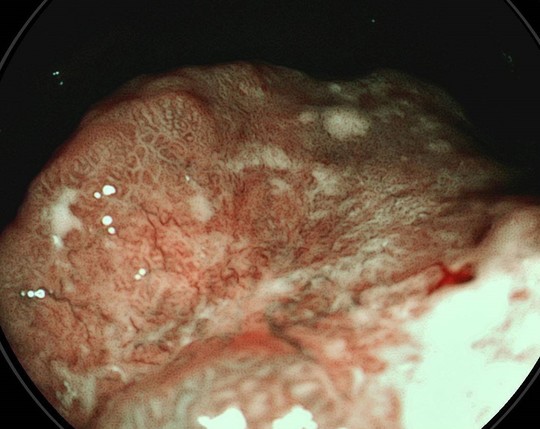

③指摘した病変を特殊光で評価

病変の内部構造を確認します。粘膜表層の血管構造をとらえ、腫瘍・非腫瘍の鑑別を行います

④病変の拡がり具合も確認

AIも利用しますが、一番大切なのは経験豊富な内視鏡専門医がしっかり診断することです。胃癌の診断では病変の範囲や深達度を評価するためにインジゴカルミンなど色素の散布を行ってより細かな診断をしていきます。